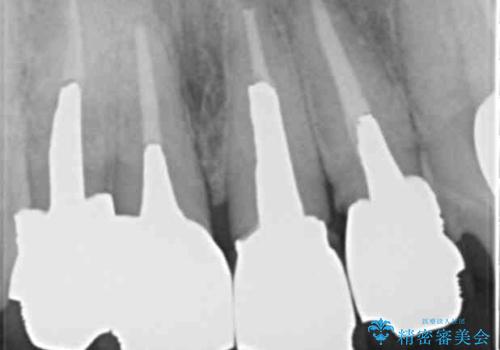

X線写真より問題のなかった根管治療は行わず、クラウンを除去し仮歯でを装着したのちジルコニアクラウンを製作していきます。

失活歯の治療について

神経をすでに取られている歯の治療を行う場合、コアを除去したのちの再根管治療を行う場合とクラウンのみやり替えする場合、状況に応じて適切な治療をご提案いたします。